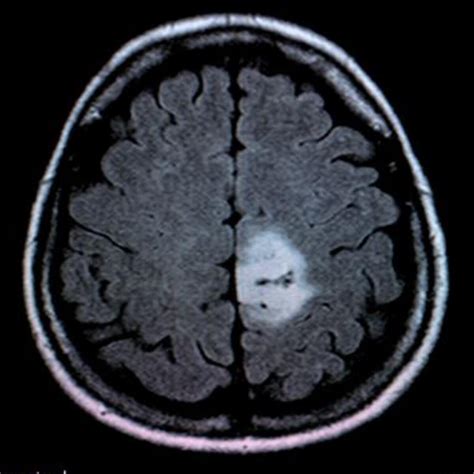

• Imaging Tests: Imaging tests such as X-rays, CT scans, MRI scans, and PET scans can help visualize the tumor or tumour and determine its size, location, and extent.

• Biopsy: A biopsy involves removing a small sample of tissue from the tumor or tumour for examination under a microscope. This can help determine whether the tumor or tumour is benign or malignant.